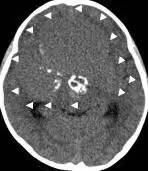

病例1:患儿男性,9岁。因反复出现意识丧失、视力降落半年收入院。入院后CT及 MRI显示颅内有形态不规则、“超大型”的颅咽管瘤,最大径约10厘米,见图1、图2。

图1.术前CT显示典型的囊性颅咽管瘤

病例二:患儿女性,7岁,主因头痛2年,精神差1个月收入院。入院时头CT见典型的“超大型”颅咽管瘤,直径约9厘米,见图6。

图6.CT显示囊性颅咽管瘤

白色三角显示肿瘤边界